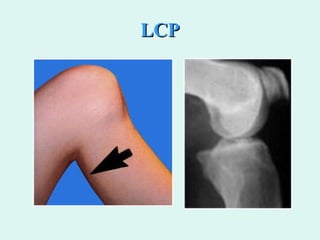

Lesión LCP Choque anterior sobre la tibia en flexión Hiperflexión  Traumatismo en apoyo

LCP

Lesión LCP Choqueanterior sobre la tibia en flexión Hiperflexión Traumatismo en apoyo